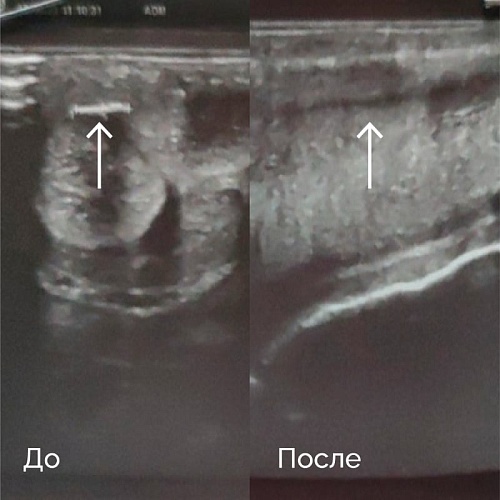

Пациент М., 32 лет

Обратился с жалобами на искривление полового члена более 30 градусов. По данным УЗИ определяется гиперэхогенное образование (бляшка) размерами 3×6 мм. Проведен курс УВТ в количестве 8 процедур. Через 6 процедур пациент отметил значительное улучшение — уменьшение искривления полового члена до 10 градусов, улучшение эректильной функции. После курса лечения пациенту проведено контрольное УЗИ полового члена, на котором дополнительных образований и включений не выявлено; кавернозные тела типичной структуры, пещеристое тело — без особенностей, эхоструктурных изменений не выявлено (рис. 2).